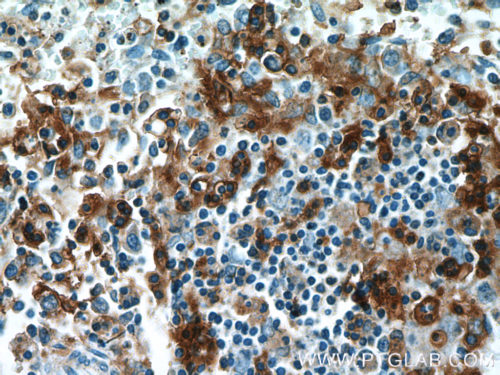

The two main types of lymphocytic leukemia are chronic lymphocytic (CLL) and acute lymphocytic (ALL). Patients have elevated levels of lymphoblasts (precursors of white cells) in their blood. These can be either T or B cell lineage. CD3 (Figure 1), CD4, and CD8, as classic markers of T cells, are a good prognostic marker of patient survival (PMID: 20846097). CD19 (Figure 2), an antigen widely present on B cells, persists in its expression on B cell-related cancer cells. It is often used in diagnosis (PMID: 8528044). Additional markers, namely CD20 (Figure 3), CD22, CD24, and CD79a, are used to study minimal residual disease – drug-resistant leukemic cells (PMID: 9492773). Plasma membrane staining of CD38 (Figure 4) and CD49d is often used in the clinic and their expression correlates with the disease severity and its response to chemotherapy (PMID: 10477712). ZAP70, an intracellular protein, is also a predictor of leukemia. It is involved in promoting prolonged signaling of the BCR pathway and the survival of cancer cells (PMID: 18577710).